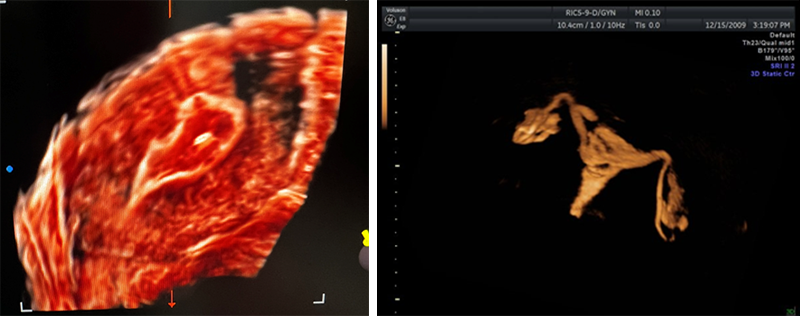

난임의 진단은 나이에 따라서 조금씩 다르지만 약 6개월에서 1년정도 부부관계를 하였는데 임신에 성공하지 못하는 경우입니다. 난임이 진단되면 난임의 원인을 밝히기 위한 기본검사를 시행합니다. 난임검사는 배란문제를 파악하기 위한 호르몬 검사, 나팔관 개통여부를 알아보는 검사, 자궁 원인을 알아보기 위한 초음파 검사 및 정액검사로 이루어져 있으며 그중 자궁원인 및 나팔관원인 파악에 초음파가 매우 중요한 역할을 합니다. 첫 내원 시 자궁근종, 선근증 및 자궁기형을 면밀하게 살피고, 난소의 종양여부 및 난관수종의 여부도 반드시 확인하여야 합니다. 이러한 과정에서 3D 초음파도 매우 자주 사용되고 있습니다. 특히 3D 초음파의 자궁기형 진단의 정확도는 매우 높습니다. 나팔관개통여부를 확인하는 방법은 엑스레이를 이용하는 방법과 초음파를 이용하는 방법이 있는데, 최근에는 비교적 외래에서 손쉽게 시행할 수 있는 초음파자궁난관조영술을 더 많이 시행하고 있습니다.